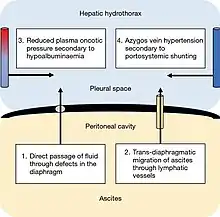

The condition is caused by portal hypertension resulting from liver disease. The causative mechanism is unknown, but several have been proposed, which are similar to those behind ascites.[2][4] The most accepted theory is that fluid originating from ascites travels through defects in the diaphragm into the pleural cavity. These defects exist in the normal population. The defects are usually less than 1 centimetre (0.39 in) and are more common on the right side, possibly because of the increased prevalence of tendon tissue from its proximity to the liver. Through a microscope, they look like discontinuities in the bundles of collagen that make up the tendon part of the diaphragm.[4] In hepatic hydrothorax, the pressure created by ascites and the thinning of the diaphragm caused by malnutrition cause the defects to become larger. Blebs of peritoneum can herniate through these defects; if they burst, a pleuroperitoneal communication is created. Fluid moves from the abdomen to the pleural cavity via a pressure gradient between the cavities. If the fluid accumulates faster than it can leave via pleural membrane absorption, hepatic hydrothorax results.[2]